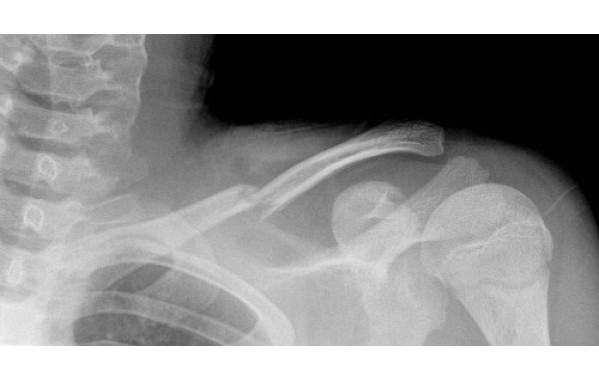

- Реабилитация после поднадкостничных переломах ключицы;

- Фиксация акромиально-ключичного сочленения;

- Разгрузка связочного аппарата ключицы;

Восьмиобразный ортез предназначен для иммобилизации грудинно-ключичного и плечевого суставов и обеспечения срастание конечности сохраняя ее полную функциональность. Он обеспечивает так называемую ранцевую повязку, которая стабилизирует ключицу, предотвращает образование ложных суставов, не ограничивая движений ребенка и сохраняя полную подвижность его руки. Помимо того, ортез активно предотвращает сутулость и помогает выработать у ребенка привычку принимать правильную осанку тела.